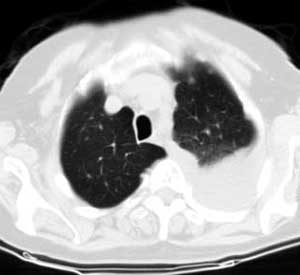

测ct值3-6hu,

既然ct值是3-6hu,还不如考虑包裹性积液。

从图片看,包裹性积液好象更合理,梭形,ct值3-5hu(在哪看到的?);胸膜间皮瘤如此规则,不多见。

左侧背部胸膜肥厚,伴包裹性积液,不考虑间皮瘤.

同意以上各位的高见,首先考虑包裹性积液,1.胸膜间皮瘤积液量一般较大,以游离性积液更为常见,2.可以看到增厚的胸膜结节